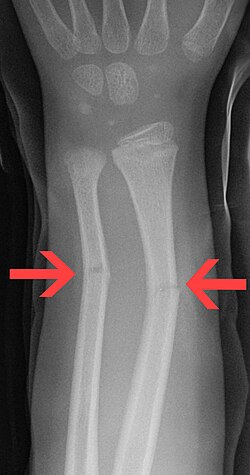

Greenstick fractures on X-ray.

On the side of the fracture that underwent tension, imaging may show bone cortex disruption. On the side that underwent compression, cortex may bulge outward, similar to a torus fracture.

Greenstick fractures are usually identified with ease on X-ray of the affected limb, showing a long bone fracture that does not cut all the way through.